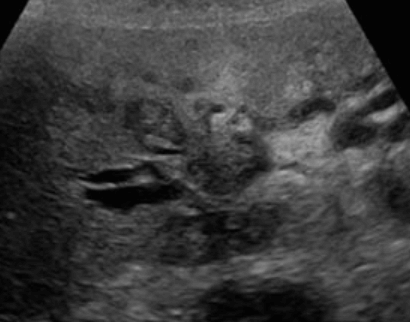

US finding

- 담관의 국소적 확장소견이 보인다.

- 불규칙하고 두꺼워진 담관벽으로 인해 담낭내강이 좁아진다.

- 담도계의 석회화.